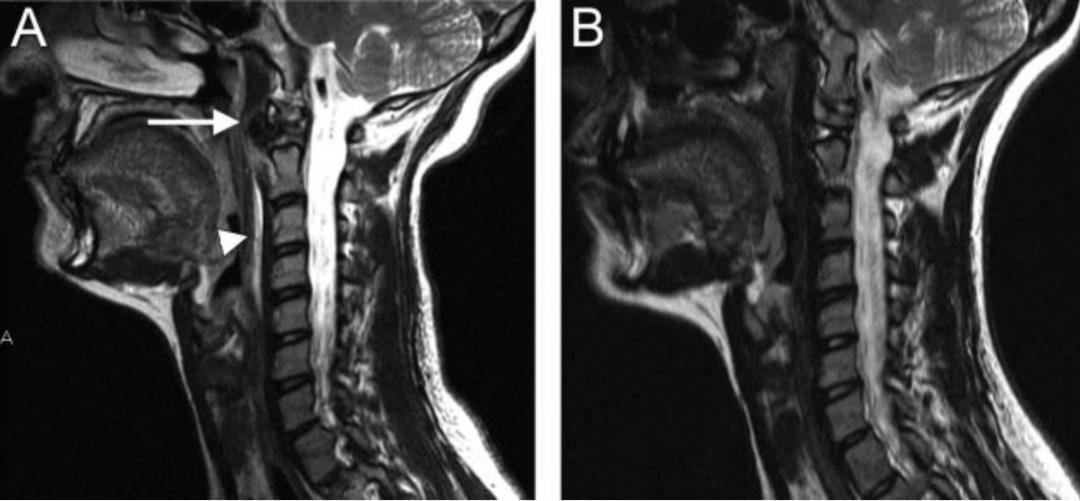

图:患者8岁,女孩,因严重颈部疼痛、活动受限伴左上肢无力、麻木不适2天就诊。既往有锁骨骨折、额部软组织挫伤病史。查体:颈椎活动受限,左上肢肌力正常,但感觉减退。白细胞、血沉、CRP升高。颈椎侧位片和CT平扫提示C6-7椎间盘钙化(粗箭头)和后纵韧带骨化(细箭头),颈椎MRI提示C6-7水平脊髓明显受压。给予颈椎制动、枕颌带2.5kg颈椎牵引2周。随后,颈托固定1个月。2年后随访复查颈椎CT如下图,同时上述症状完全缓解。

图:8岁女孩,因颈腰痛伴左上肢放射痛2月余就诊,颈椎侧位片、CT和MRI表现与上述病例类似。

36岁女性,急性颈痛、吞咽困难伴颈部僵硬,MRI示C1-2前部颈长肌增厚呈低信号,提示钙化(长箭头)和C1-4椎前积液(无线箭头),经类固醇和止痛药治疗8天后症状消失,复查MRI提示上述表现消失。(PMID: 18765656)

30岁女性,诊断为颈长肌钙化性肌腱炎,但钙化位于不寻常的位置:C4-5椎间隙前侧。A:颈椎侧位片示寰枢椎半脱位(长箭头)和椎前软组织肿胀(无线箭头);B,C和D:颈椎MRI示C1-6椎前软组织肿胀伴积液,D示齿状突骨侵蚀(无线箭头)